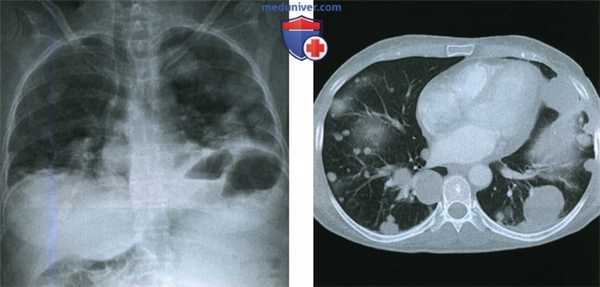

(Слева) Рентгенограмма грудной клетки в заднепередней проекции пациентки 52 лет, которая 15 лет назад подверглась гистерэктомии по поводу миомы матки: множественные узелки различных размеров в обоих легких.

(Справа) При КТ с контрастным усилением в аксиальной плоскости (легочное окно) у той же пациентки в обоих легких видны множественные солидные узелки различных размеров с четкими границами. (Слева) При КТ с контрастным усилением в аксиальной плоскости у той же пациентки в обоих легких видны многочисленные солидные узелки с четкими границами. Узелки имеют однородную структуру, по рентгеновской плотности соответствуют мягким тканям и слабо накапливают контрастное вещество.

(Справа) При КТ с контрастным усилением в аксиальной плоскости (легочное окно) у той же пациентки в обоих легких видны множественные солидные узелки различных размеров с четкими границами.